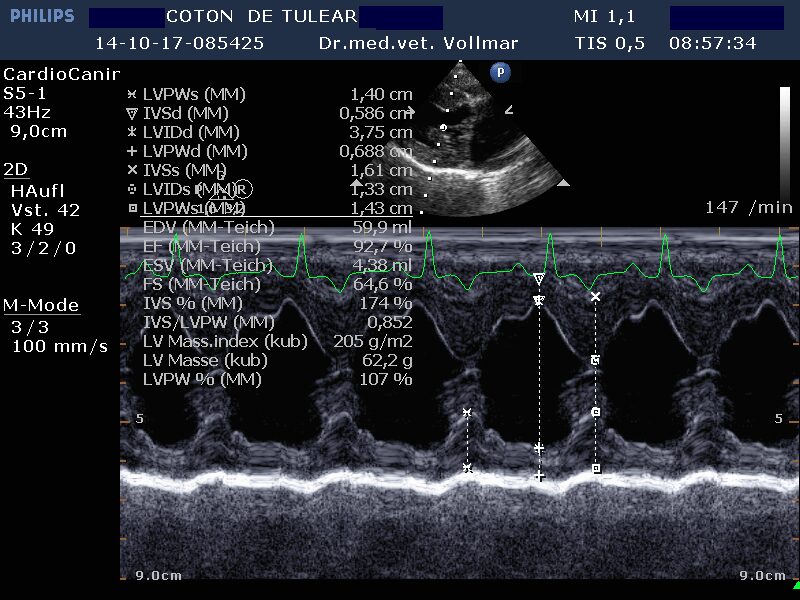

Am sichersten kann die Größe der einzelnen Herzabteilungen und der Schweregrad einer AV-Klappeninsuffizienz mit Hilfe der Echokardiografie beurteilt werden. Die Messung der Vorhofgröße vorzugsweise im 2D-Bild korreliert zuverlässig mit dem Ausmaß der MI. Mittels verschiedener Doppler- und Farbdoppler-Analysemethoden kann die Größe der Lücke in der Mitralklappe bestimmt und das regurgitierte Blutvolumen ermittelt werden.

Die degenerative Mitralklappeninsuffizienz (MI) stellt beim Hund die Hauptursache für ein kongestives Herzversagen und kardial bedingten Tod dar. Im Krankheitsverlauf vergrößert sich mit zunehmender Schwere der Klappeninsuffizienz zunehmend der linke Vorhof und das diastolische Ventrikelvolumen nimmt zu, während das systolische Ventrikelvolumen erst mit nachlassender Kontraktilität bei Entwicklung einer Volumenüberlastungskardiomyopathie zunimmt. Bei kleineren Hunden unter 15 kg Körpergewicht ist dies oft erst später im Krankheitsverlauf der Fall, bei größeren Hunden über 15 kg hingegen häufig früher.

Nach derzeitigem Kenntnisstand ist bei MI eine Medikation immer erst dann sinnvoll, wenn bereits eine Herzvergrößerung vorliegt.